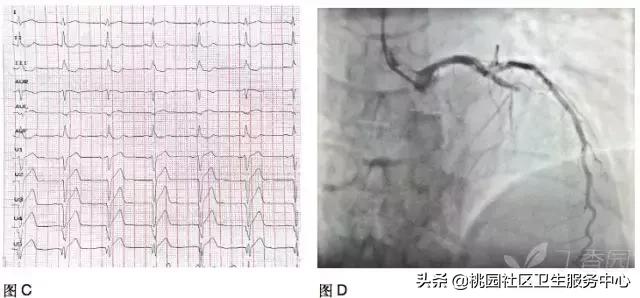

男性,59 岁,胸骨后疼痛伴大汗 8 小时;图 A:发病 1 小时诊:V1~4 的 T 波高尖;图 B:发病 3 小时症状好转:V1~5 ST 段上斜型压低;图 C:发病 8 小时入院:病理性 Q 波形成;图 D:急诊 PCI:LM 斑块,近端狭窄 40%,LAD 近端闭塞,LCX 中段狭窄 70~80%,右冠多发斑块,中段狭窄 70~80%;